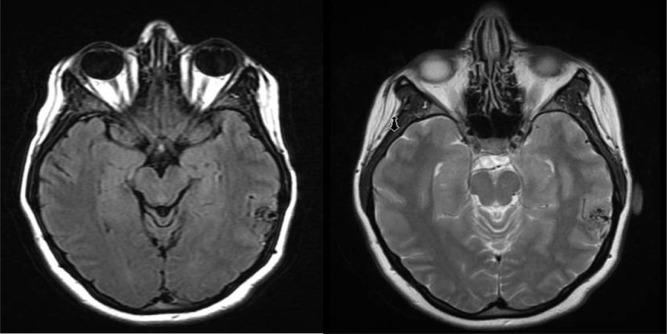

With rapidly increasing numbers of neuroendovascular procedures performed annually in recent years, use of arterial closure devices after femoral artery access has been exceedingly common secondary to reduced time to hemostasis, decreased patient discomfort, earlier mobilization, and shortened hospital stay. Although uncommon, use of these devices can lead to a different spectrum of complications, as compared to manual compression. Ischemic symptoms following the use of these devices can have unexpected clinical sequelae and can occur in a delayed fashion. Awareness and recognition of such complications is important with the dramatically increased use of these devices in recent years. We report on a case of delayed vascular complication manifesting as vascular claudication following use of the AngioSeal closure device.

近年来,随着每年进行的神经血管内手术数量迅速增加,股动脉穿刺后使用动脉闭合装置极为普遍,这是因为止血时间缩短、患者不适感减轻、能更早活动以及住院时间缩短。与手动压迫相比,虽然这些装置的使用并不常见,但可能导致一系列不同的并发症。使用这些装置后的缺血症状可能会产生意想不到的临床后果,并且可能延迟出现。鉴于近年来这些装置的使用显著增加,认识和识别此类并发症很重要。我们报告一例使用血管封堵器(AngioSeal)后出现延迟性血管并发症,表现为血管性跛行的病例。